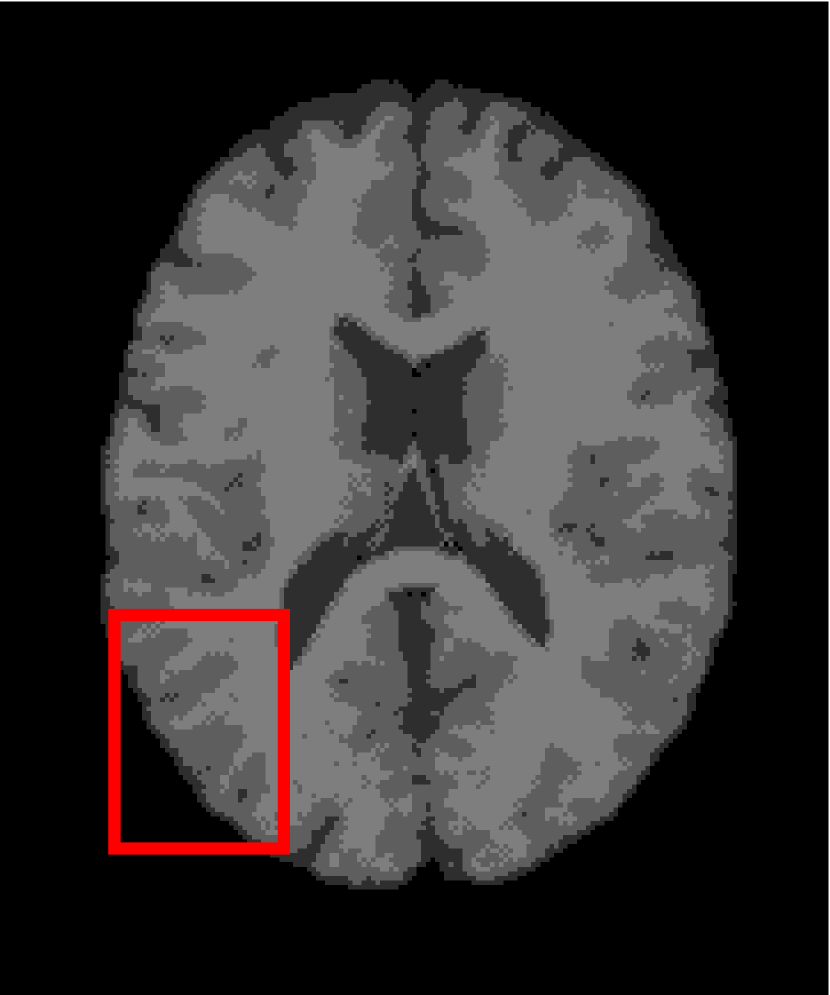

Next, we representatively segment five medical images from BrianWeb. They are represented as five slices in the axial plane with a sequence of 70, 80, 90, 100 and 110, which are generated by T1 modality with slice thickness of 1mm resolution, 9% noise and 20% intensity non-uniformity. Here, we set c=4𝑐4c=4 for all cases. The comparison between WRFCM and its peers are shown in Fig. 9 and Table II. The best values are in bold.

Figure 9: Segmentation results on five medical images. The parameter: ϕ=5.35italic-ϕ5.35\phi=5.35. From top to bottom: noisy images, ground truth, and results of FCM_S1, FCM_S2, FLICM, KWFLICM, FRFCM, WFCM, DSFCM_N, and WRFCM.

By a view of the marked red square in Fig. 9, we find that FCM_S1, FCM_S2, FLICM, KWFLICM and DSFCM_N are vulnerable to noise and intensity non-uniformity. They give rise to the change of topological shapes to some extent. Unlike them, FRFCM and WFCM achieve sufficient noise removal. However, they produce overly smooth contours. Compared with its seven peers, WRFCM can not only suppress noise adequately but also acquire accurate contours. Moreover, it yields the visual result closer to ground truth than its peers. As Table II shows, WRFCM obtains optimal SA, SDS and MCC results for all five medical images. As a conclusion, it outperforms its peers visually and quantitatively.